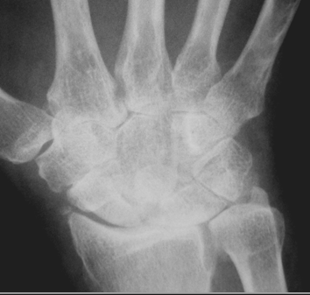

Fig 102. Artropatía reumática.

Rx AP. Signos de osteopenia generalizada, de predominio periarticular.